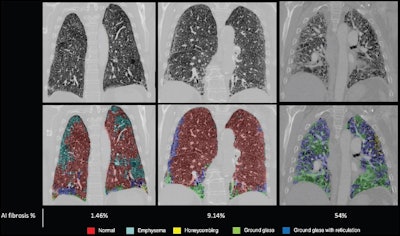

The team found that higher, AI-quantified percentages of fibrosis translated to increased risk of patient mortality in the training cohort (hazard ratio, 1.01, with 1 as reference), a result validated in the external test cohort (C index, 0.76, with 1 as reference). Additionally, the model that combined AI-quantified fibrosis and radiologic scoring demonstrated improved performance for predicting patient mortality compared with a model that consisted of radiologic scoring alone, with a C index of 0.67 compared with 0.61 (p < 0.001).

Examples of degrees of fibrosis quantified and radiologically scored. CT pulmonary angiograms (top row) were radiologically scored as having mild (left), moderate (middle), and severe (right) disease; the corresponding output and fibrosis percentage as quantified by the artificial intelligence (AI) model are shown in the bottom row. Images courtesy of the RSNA.

"[We found] that artificial intelligence (AI)-quantified fibrosis at CT was prognostic for survival in patients with pulmonary hypertension and lung disease," the group wrote. "This was independent of demographic characteristics … [and] hemodynamic disease severity … and was externally validated in images from 37 centers. The second key finding of our study is that the AI model was sensitive to minor parenchymal differences and, when used in combination with radiologic reporting, provided additional predictive prognostic value … [compared to] radiologic scoring alone."